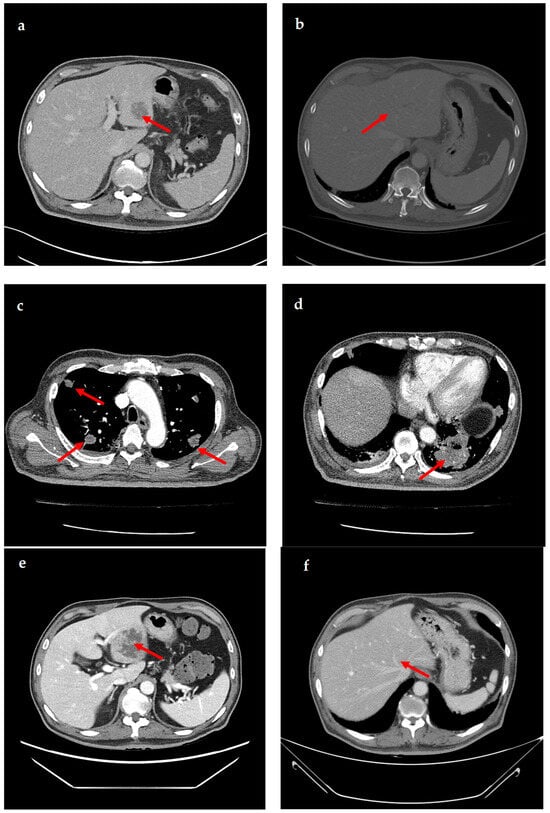

A 69-year-old male patient presenting with severe toothache 10 days before admission and melena 3 days before admission was admitted to the Infectious Disease Department of Kyung Hee University Hospital in the Republic of Korea in March 2025. The patient reported worsening toothache in the right upper gingiva with right facial swelling that began 5 days after a dental implant surgery at the upper right first premolar. Subsequently, the patient underwent incision and drainage at a local dental clinic one day before admission because of periodontitis that had spread to the facial area, as confirmed through the patient’s medical history. The patient had diabetes and was taking hypoglycemic agents. He had undergone coronary artery bypass grafting (CABG) for myocardial infarction 13 years previously. Additionally, he had undergone a prostatectomy for prostate cancer 2 years ago. He had been continuously taking clopidogrel (an antiplatelet agent) since undergoing CABG. The right buccal area of the face was swollen. Dental examination revealed a space abscess around the upper right first premolar (Figure 1). Panoramic dental X-ray showed that the implant fixture was placed in the alveolar bone of the upper right first premolar, and the external part has been removed (Figure 2). The implant fixture at the upper right first premolar was removed and irrigation and drainage were performed at the upper right first premolar and the vestibular area of the upper right second incisor, canine, and first premolar. The initial vital signs were blood pressure, 124/73 mmHg; pulse rate, 87 beats/min; respiratory rate, 20 breaths/min; temperature, 36.5 °C, oxygen saturation level, 98% on room air. Laboratory examination revealed a white blood cell (WBC) count of 6.23 × 109/L (83.0% neutrophils) and a C-reactive protein (CRP) level of 417.0 nmol/L. The aspartate aminotransferase, alanine aminotransferase, and alkaline phosphatase levels were 46, 57, and 97 IU/L, respectively. The serum creatinine level was 1.08 mg/dL and the BUN was 40 mg/dL. The serum sodium level was 129 mEq/L. Plasma level of glycated hemoglobin was 13.5%. Chest computed tomography revealed a mass-like lesion in the left lung with multiple small nodules in both lungs. Two sets of blood cultures were performed on the day of admission using BD Bactec Plus Aerobic/F and BD Bactec Plus Anaerobic/F bottles and a Bactec FX Instrument (Becton Dickinson, Sparks, MD, USA). The patient underwent esophagogastroscopy, which revealed active bleeding from multiple duodenal ulcers and subsequently received hemostatic treatment. A gastrointestinal bleeding dynamic computed tomography (CT) scan showed a liver abscess at S2/3 (3.1 cm) (Figure 3a) with focal septic thromboembolism in the left hepatic vein (Figure 3b). Chest CT revealed mass-like consolidation and air densities in the left upper and lower lobes, along with multiple irregular nodules with ground-glass opacities in both lungs (Figure 3c,d).

Figure 1. Clinical photography of initial dental examination. The external part of implant at upper right first premolar had already been removed at local dental clinic. Irrigation and drainage were performed at the upper right first premolar and the vestibular area of the upper right lateral incisor, canine, and first premolar. The implant fixture at the upper right first premolar was removed.